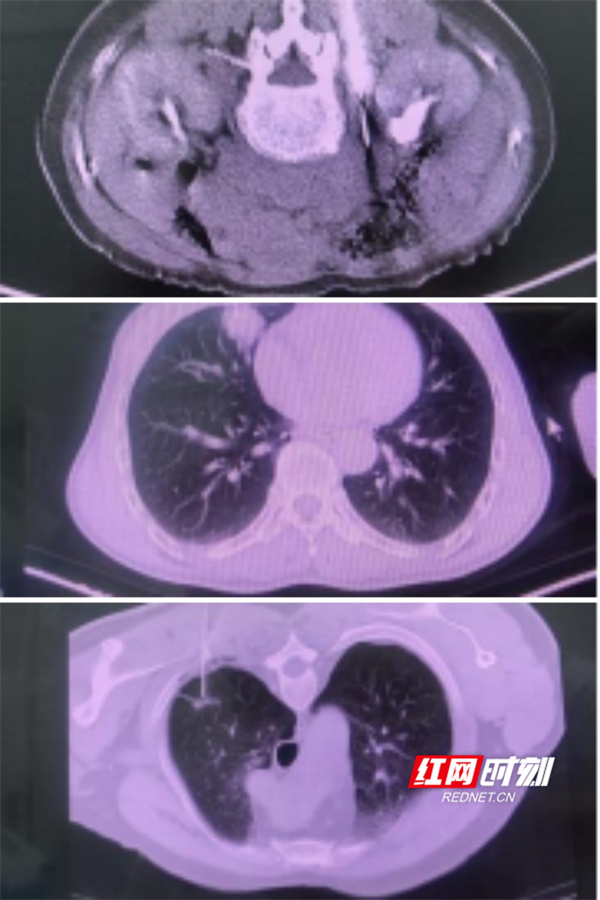

市中心医院肿瘤科作为国家临床重点专科培育项目建设单位,始终致力于提升医疗服务水平。此次南华大学附属第一医院肿瘤科专家团队入驻后,双方开展深度交流,从系统讲解穿刺活检术的理论知识、操作要点及术中术后风险应对方案,到全程示范操作流程;从术前影像评估、穿刺点精准定位,到术中穿刺取样、术后观察护理,每个环节帮扶专家都细致指导,逐一解答医护人员疑问。帮扶期间,市中心医院肿瘤科已成功完成3台高难度手术,包括1台贴近心脏危险部位肿块穿刺活检、1台8毫米肺部小结节穿刺活检以及1台腹膜后深部肿块穿刺活检。所有手术一气呵成,成功率达100%,患者术后恢复良好。

“这个靠近心脏的肿块,好几家本地医院都不敢做穿刺,没想到在这儿顺利确诊了!”患者秦先生的家属难掩感激。秦先生是鼻咽癌放化疗后4年的患者,复查时发现胸部肿块,此次手术不仅让他避免了奔波省级医院的麻烦,更大幅减轻了经济负担。